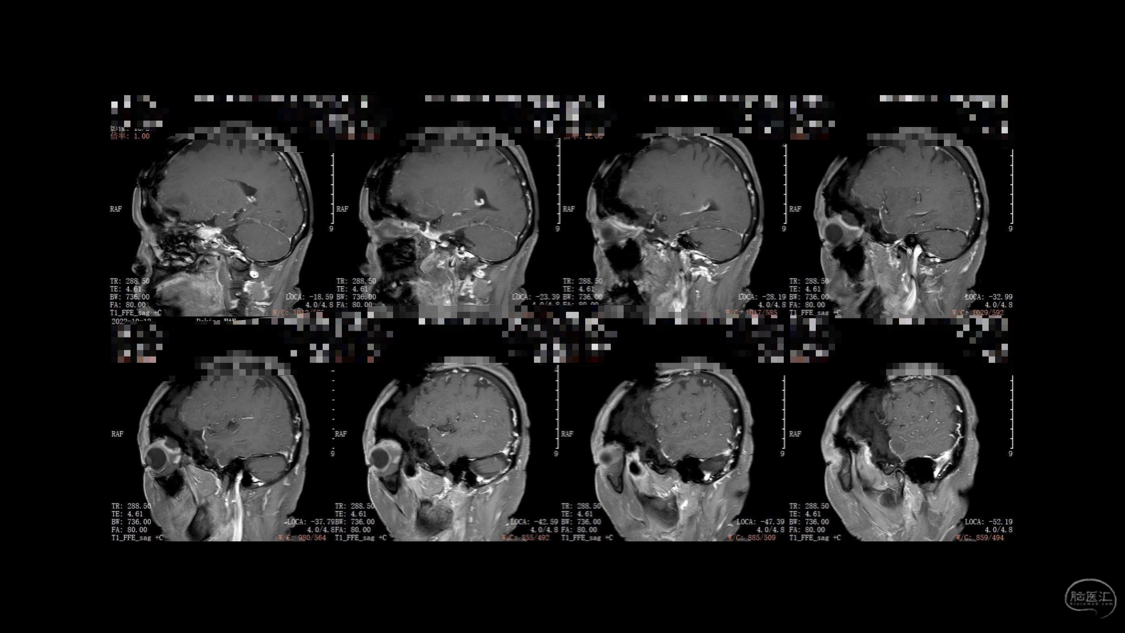

陈保东教授手术作品-右眶内及海绵窦旁孤立性纤维瘤